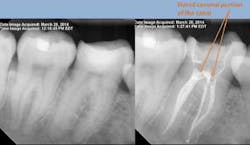

Once the canals are located, I’ll use a 0.10 Sybron TF rotary file to enlarge the coronal third and remove pulp tissue. Now that the canals are visible, widen the coronal portion further using Gates Glidden. Flaring the coronal portion is vital to preventing file fractures and ensures adequate instrumentation and irrigation during the procedure. All of the canals should be easily visible for good access.

Once all of the canals are found, I will go through the series of Sybron Twisted Files size 25 tapering from 0.10 to 0.80 to 0.60 to 0.40. The 0.40 file should reach the working length for most canals. On a large palatal or distal canal, the 0.60 TF will usually reach working length. After which, using the crown-down technique with the Brasseler EndoSequence rotary files, instrument each canal until files reach the working length. Once instrumentation is complete, take a P.A. with gutta-percha to confirm instrumentation to working length. I find it much easier to take working length films with gutta-percha rather than files (which may fall out, bend, or separate)